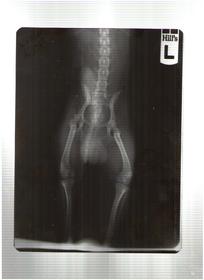

Выкладываю рентгеновский снимок чтобы Вы помогли определиться с диагнозом и определить степень болезни.

• 1_Снимок.jpg

Чихуахуа (Снимок.jpg)

Мария81, вам нужен грамотный травматолог, дисплазия - не основной диагноз, на мой взгляд у собаки явная проблема в недостатке хрящевой ткани - почему? нужно разбираться

на данном снимке Перерсона не вижу 9хотя, он не исключен)